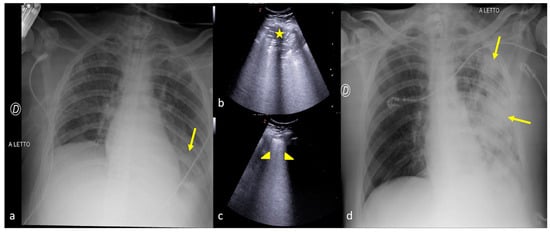

2.1. Atelectasis

2.3. Pleural Effusion